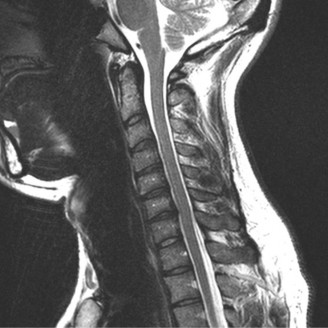

Determine the most appropriate treatment of different types of Hangman’s fractures? CASE 14 A 70-year-old retired, funeral director presents with symptoms of right upper extremity numbness and weakness. He reports that he developed acute neck and right upper arm pain while undergoing a dental procedure. Treatment so far has been nonsteroidal anti-inflammatory medication and physical therapy with cervical traction. While his pain improved with this course of treatment, he has ongoing paresthesias radiating into his right hand and weakness affecting his right upper extremity. Figures 1–20 and 1–21 show a midsagittal and axial image through C6–7, respectively.

Figure 1–20

Figure 1–21

The correct answer is (A). Considering the patient’s complaints and the imaging, he most likely has radiculopathy, probably secondary to a disc-osteophyte complex associated with foraminal stenosis at the C6–7 level. There is no suggestion in the history of walking imbalance or dexterity issues in the upper extremities. Thus, a diagnosis of myelopathy is less likely. Furthermore, the degree of spinal compression is mild and not likely (though not impossible) to cause spinal cord dysfunction. An intradural tumor would have a different MRI appearance, likely demonstrating an area of high signal within the parenchymal tissue of the spinal cord itself. A central cord syndrome is an acute spinal cord injury with upper extremities being affected more than lower extremities.

The correct answer is (C). The patient has nerve root compression at the C6–7 level, which would affect the exiting C7 nerve. Weakness of right elbow extension and wrist flexion with sensory loss of the middle finger are the most likely findings.